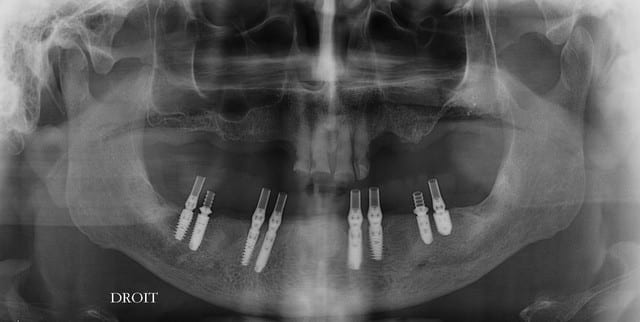

Quand je fais des EMCI totale sur 6 à 8 implants avec appui osseux

je pose les implants puis les piliers qui sont l’équivalent de couronnes télescopiques, et le bridge à armature métallique sans scellement ni vis, dans la même séance

La prise d'empreinte s'est faite en occlusion en se servant de fac simile translucides en résine préparés à partir de la prothèse totale haut et bas fabriquée dans un premier temps.

Le prothésiste n'a eu qu'à présenter le complet du bas sur la mise en articulateur obtenue après la chirurgie pour aménager celle ci en prothèse à transvisser. Ce que je crois c'est que les guides ne permettent pas de changer son fusil d'épaule en cours de chirurgie et qu'il est impossible de prédire un trajet de forage idéal sur base des data radiologiques. Il y a très souvent matière à faire autrement lorsqu'on ouvre le lambeau, même lorsque la préparation a été minutieuse. ... Et surtout ne venez pas prétendre parvenir à enfouir les spires parfaitement en se servant de guides figés, il doit y avoir des crêtes qui lâchent au forage ou au vissage de l'implant et quid des crêtes déchiquetées ou tortueuses qu'il est indiqué de raboter au préalable ? J'ai difficile accepter l'idée que de faire coller la position des implants à une prothèse déjà terminée est un bon chemin, tout ça pour que le patient sorte avec des dents séance tenante. On n'est pas dans une usine de fabrication de bagnoles...

J'ai difficile imaginer, je me répète, qu'il soit possible de poser une prothèse immédiate PASSIVE sur huit implants posés en se servant d'un guide... Je dis bien PASSIVE. Lors de la réalisation du cas présenté je n'avais pas de tierce personne pour faire les photos, c'est dommage pour moi, mais la seconde prothèse renforcée par une armature ISUS a été réalisée sur le premier modèle de travail et il n'y a pas eu d'essayage, c'est rentré pile poil sans forcer. Où est le souci de poser quelques heures plus tard ?